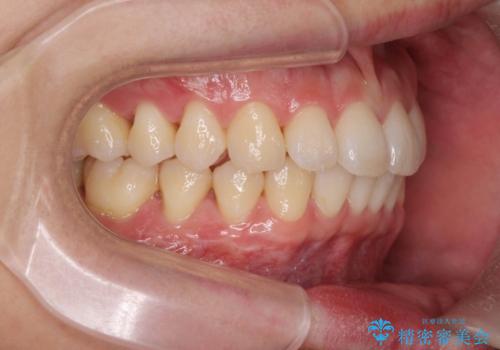

- 20代男性

- ワイヤー

- 10ヶ月

- 取り外しの必要なマウスピース矯正ではなくワイヤー矯正を希望され来院されました。

マウスピース矯正、ワイヤー矯正どちらの方法でも治療は可能ですが、ご要望の通りワイヤー矯正で歯の排列を行っていきます。